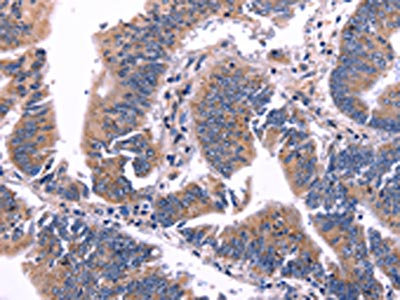

The image on the left is immunohistochemistry of paraffin-embedded Human colon cancer tissue using CSB-PA906268(ARC Antibody) at dilution 1/50, on the right is treated with fusion protein. (Original magnification: ×200)

The image on the left is immunohistochemistry of paraffin-embedded Human brain tissue using CSB-PA906268(ARC Antibody) at dilution 1/50, on the right is treated with fusion protein. (Original magnification: ×200)